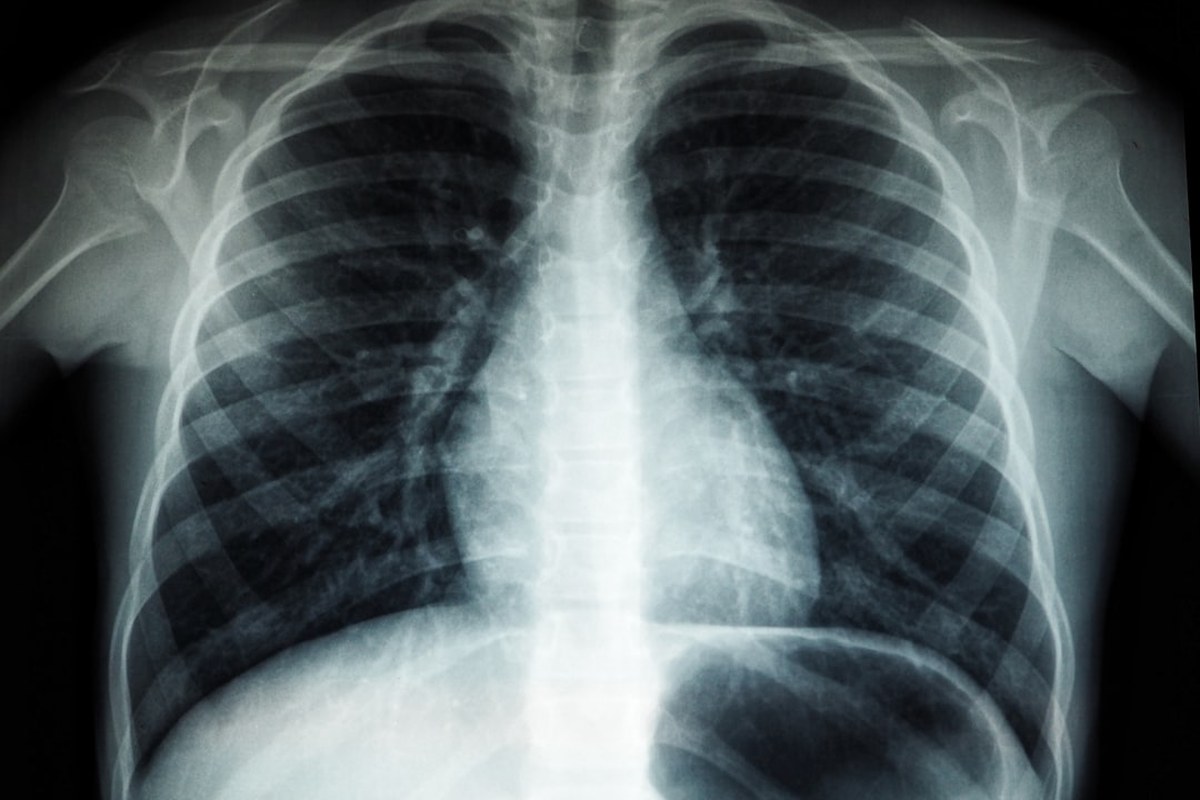

놓치면 안 되는 치료 시기

소세포폐암은 진행 속도가 매우 빠르기 때문에, 진단 후에도 빠르게 치료를 시작하는 것이 중요합니다.

“진단 후 불과 몇 주 만에 병기가 달라질 수 있을 만큼 소세포폐암은 진행 속도가 빠르므로 완치를 목표로 삼을 수 있는 제한병기에서의 치료 시기를 놓치지 않아야 합니다.”

제한병기일 때 치료를 시작하는 것이 완치 가능성을 높이는 열쇠입니다.